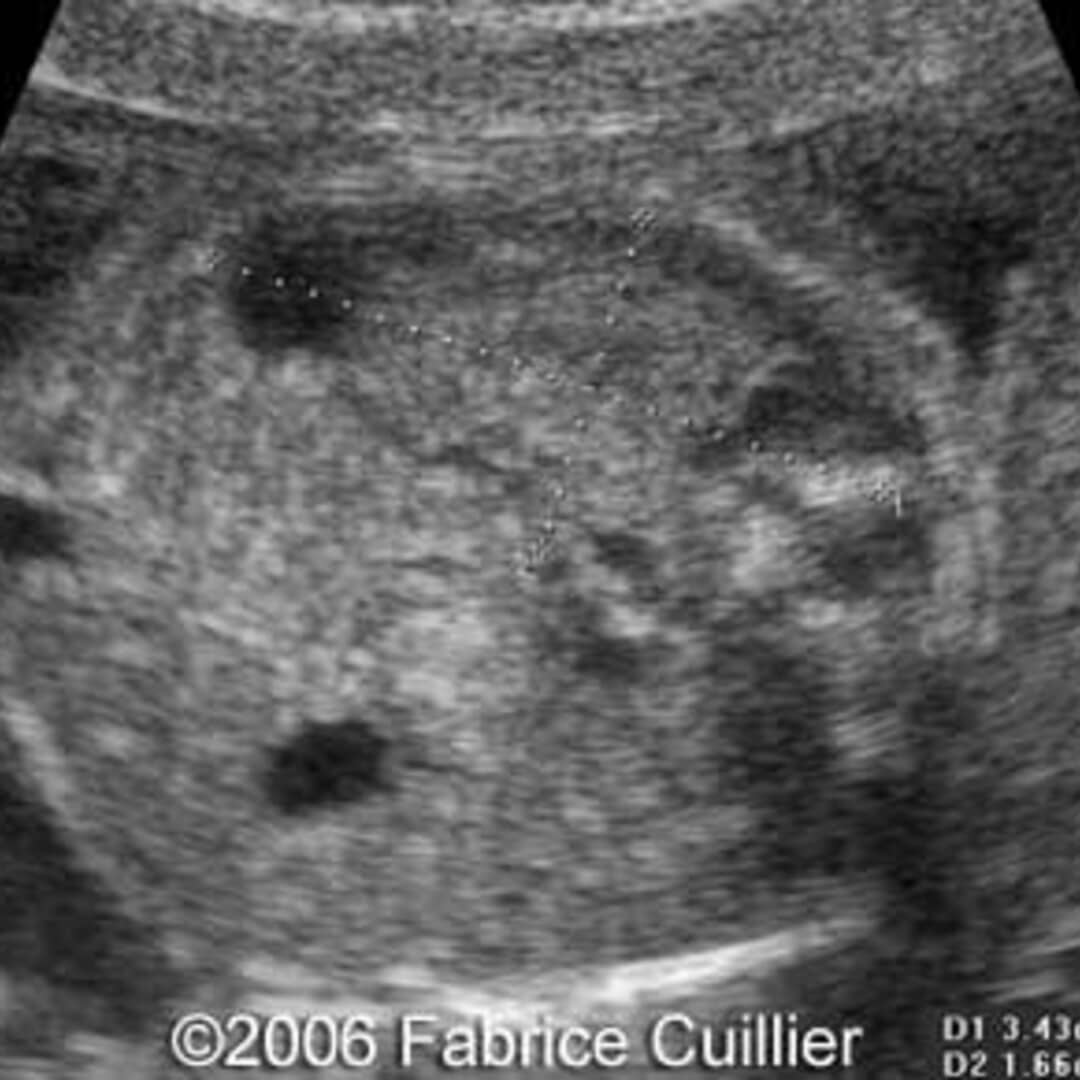

The ultrasound images of multicystic dysplastic kidney (MCDK). (A Horseshoe Kidney With Unilateral Multicystic Dysplasia — horseshoe kidneys are the most common type of renal fusion anomaly. multicystic dysplastic changes in one half of a horseshoe kidney is an uncommon presentation. — multicystic dysplastic kidney is a form of renal dysplasia characterized by the presence of multiple, noncommunicating cysts. They render the kidneys susceptible to trauma and are an. horseshoe kidney. Horseshoe Kidney With Unilateral Multicystic Dysplasia.